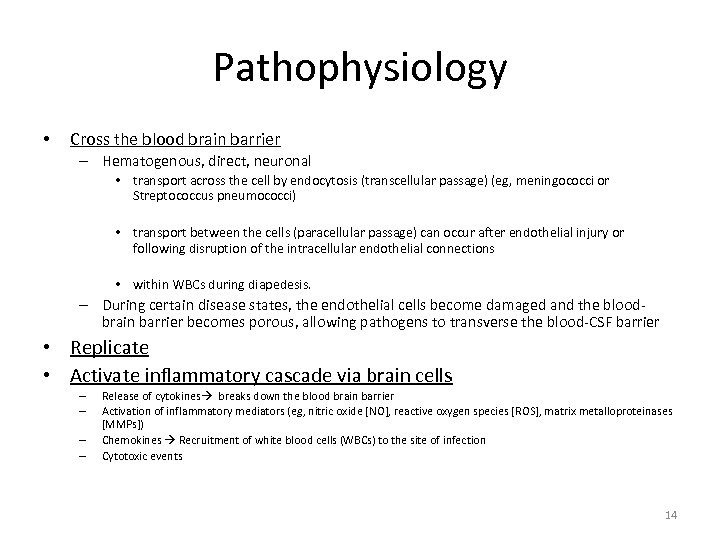

Pathophysiology • Cross the blood brain barrier – Hematogenous, direct, neuronal • transport across the cell by endocytosis (transcellular passage) (eg, meningococci or Streptococcus pneumococci) • transport between the cells (paracellular passage) can occur after endothelial injury or following disruption of the intracellular endothelial connections • within WBCs during diapedesis. – During certain disease states, the endothelial cells become damaged and the bloodbrain barrier becomes porous, allowing pathogens to transverse the blood-CSF barrier • Replicate • Activate inflammatory cascade via brain cells – – Release of cytokines breaks down the blood brain barrier Activation of inflammatory mediators (eg, nitric oxide [NO], reactive oxygen species [ROS], matrix metalloproteinases [MMPs]) Chemokines Recruitment of white blood cells (WBCs) to the site of infection Cytotoxic events 14